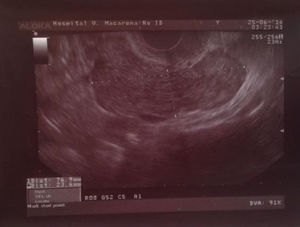

La exploración ginecológica mostraba movilización cervical dolorosa y defensa a la palpación abdominal profunda en fosa ilíaca izquierda. En la ecografía transvaginal no se apreciaron alteraciones significativas en útero y ovario derecho; en la zona anexial izquierda existía una imagen de contenido hipoecoico, tubular de 76,9×23,6mm, que al corte transversal ofrecía una morfología en rueda de carro, sugestiva de piosalpinx (fig. 1).

La principal técnica diagnóstica en el cáncer de trompa es la ecografía transvaginal1. La imagen ecográfica característica es la de una masa pélvica independiente del útero y del ovario en forma de salchicha, «sausage-shaped mass»1. Una masa sólida, papilar, intratubárica también debe hacer sospechar un cáncer de trompa9. La presentación más frecuente en la serie de Patlas et al.9 de estos tumores es la de una masa sólida pélvica, correspondiente con la localización esperada de la trompa, en asociación con ovarios visibles normales. El hecho de que dicha masa sea móvil refuerza la sospecha diagnóstica9.

Ecográficamente, los cánceres de trompa pueden simular otras enfermedades anexiales que suelen presentarse con mayor frecuencia, como embarazo ectópico, absceso tuboovárico o hidrosalpinx, quiste paraovárico, mioma pediculado, absceso diverticular, absceso o tumor apendicular, enfermedad maligna o inflamatoria intestinal y riñón pélvico, por lo que no es infrecuente la confusión diagnóstica con estos cuadros. Ante la sospecha fundamentada en los medios diagnósticos antes expuestos, la laparotomía o laparoscopia exploradora pueden ser de gran ayuda.10